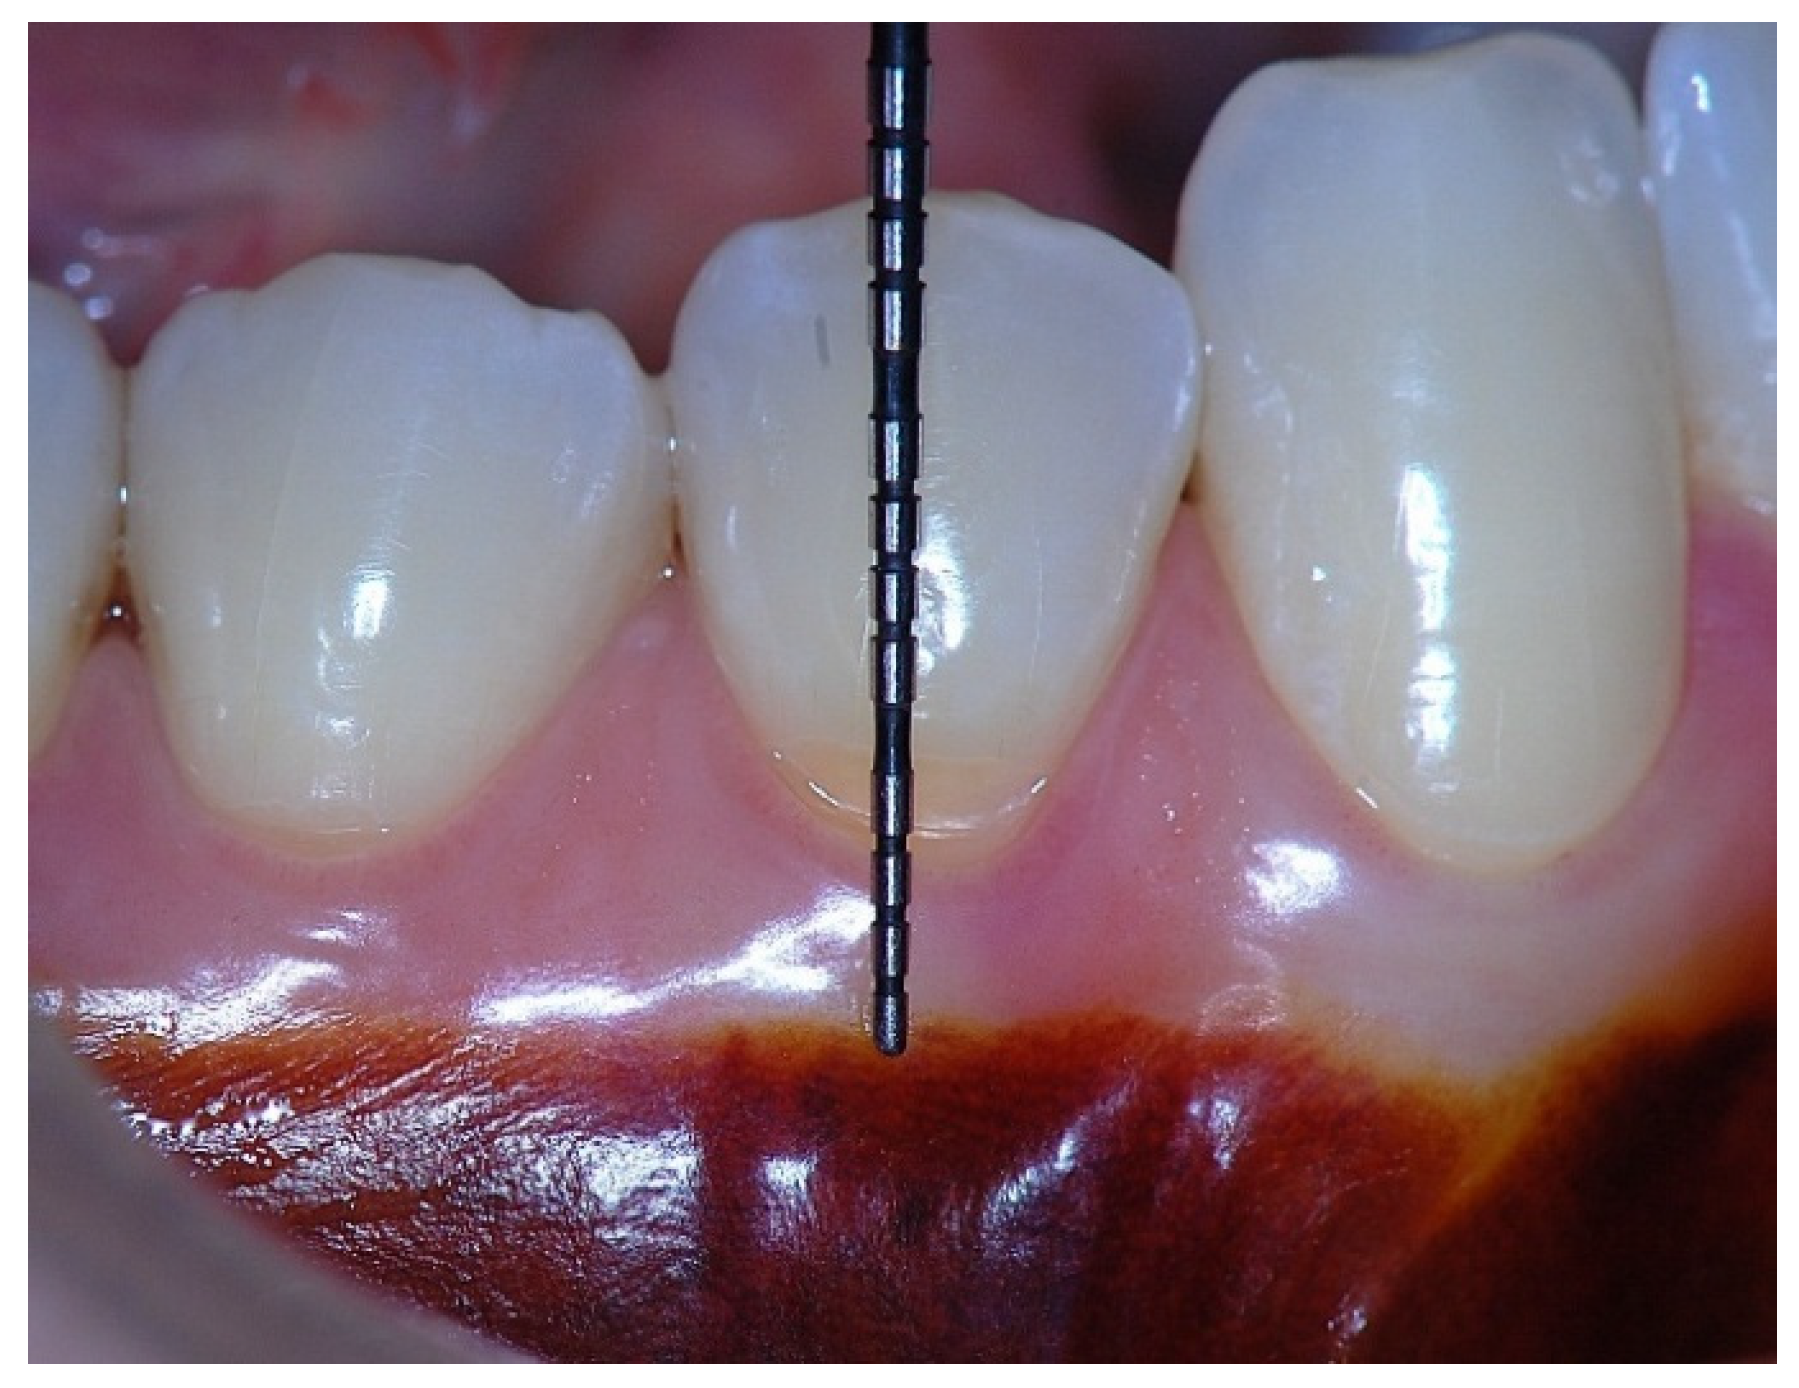

Figure 4. Probing depth of 1 mm associated with 1 mm of epithelial attachment and 1 mm of connective tissue fiber insertion into the root cementum.

In a clinical scenario characterized by 2 mm of keratinized tissue and a sulcus depth of 1 mm, a stable and mechanically resistant connective tissue attachment is not present [1]. This is attributable to the fact that most connective tissue fibers inserting into the root surface are associated with non-keratinized, mobile mucosal tissues (Figure 1), which are elastic in nature and therefore incapable of stabilizing the gingival margin (Figure 2 and Figure 3). In contrast, when these fibers are embedded within keratinized tissue, they are firmly anchored to both the tooth and alveolar bone and are comparatively immobile, thereby contributing to gingival margin stability (Figure 4, Figure 5 and Figure 6).

To achieve predictable resistance to mechanical trauma, a keratinized tissue width of approximately 3 mm appears necessary, assuming a sulcus depth of 1 mm, thereby allowing for 1 mm of epithelial attachment and 1 mm of dense connective tissue attachment to the root surface [21,33].

Clinically, an ideal scenario involves a keratinized tissue width of ≥3 mm, as this configuration supports connective tissue fiber insertion into both the root surface and the periosteum of the alveolar bone (Figure 7, Figure 8, Figure 9, Figure 10 and Figure 11). Notably, a KT width ≥3 mm represents the only condition that fully aligns with classical definitions of attached gingiva in the periodontal literature and with American Academy of Periodontology criteria, which describe AG as being firmly attached to the underlying alveolar bone and root cementum by dense connective tissue fibers [1,3,34,35].